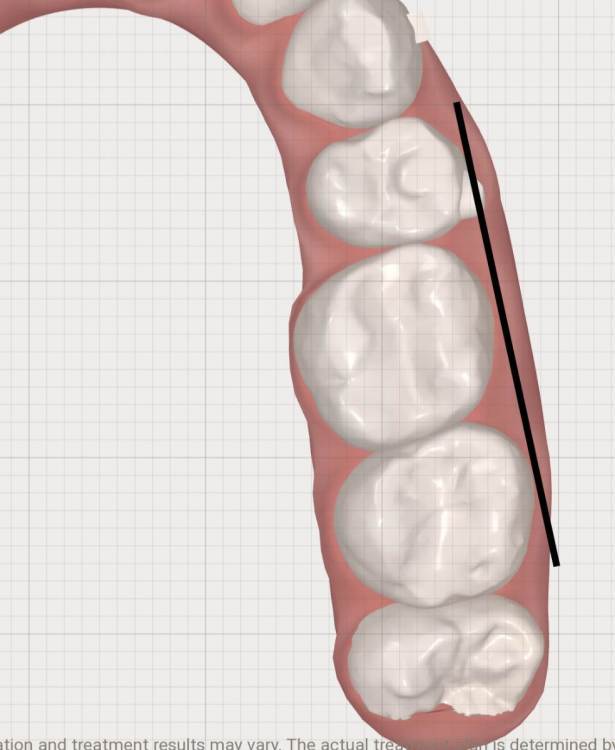

АнтонТЛТ Опубликовано 5 января, 2022 Поделиться Опубликовано 5 января, 2022 (изменено) Если провести воображаемую линию по режущим краям передних зубов и по щечным буграм жевательных зубов верхней челюсти то должна получиться элиптическая линия без ступенек, в Вашем случае не все зубы довернуть. Изменено 5 января, 2022 пользователем АнтонТЛТ 1 Ссылка на комментарий

АнтонТЛТ Опубликовано 5 января, 2022 Поделиться Опубликовано 5 января, 2022 (изменено) Нижняя челюсть должна иметь параболическую форму. Видно, что нижний левый первый моляр находится в более язычном положении, его наклон в передне-заднем направлении исправили, но наклон в щечно-язычном направлении остался. Нижний правый второй моляр тоже расположен более язычно по сравнению с соседними зубами. Изменено 5 января, 2022 пользователем АнтонТЛТ Ссылка на комментарий